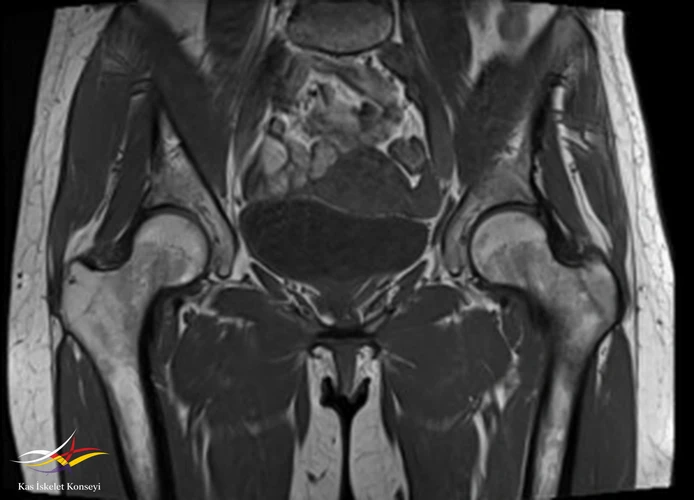

İncelemeler: Kalça MRG ve BT incelemelerinde sol femur trokanter major bölgesinde kemik iliği ödemi, bilateral şüpheli trokanterik bölge fraktür hattı, trokanterik bursit ile uyumlu görünüm saptandı.

Resim 1. Koronal T1 ağırlıklı MRG incelemesi.